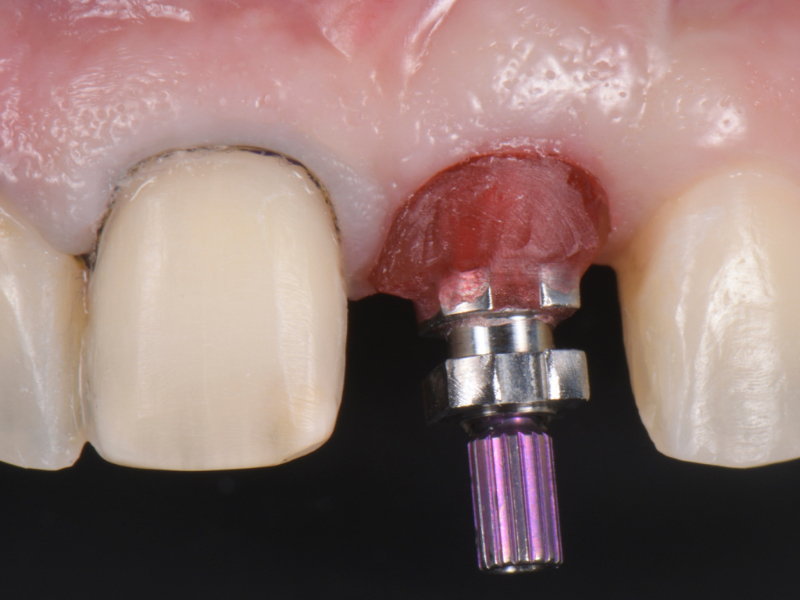

Once the optimal emergence profile has been developed, we need to communicate and transfer this information properly to the laboratory. Unfortunately, all implant companies provide stock round impression copings that do not precisely transfer the soft-tissue contours. A simple protocol to communicate this information is described here.

This visual essay walks through a step-by-step description of how to fabricate a personalized impression coping with transfer ofthe peri-implant tissue anatomy properly.

A step-by-step technique for fabricating a personalized impression coping was described to optimize the transfer of the peri-implant soft tissue architecture to the laboratory.